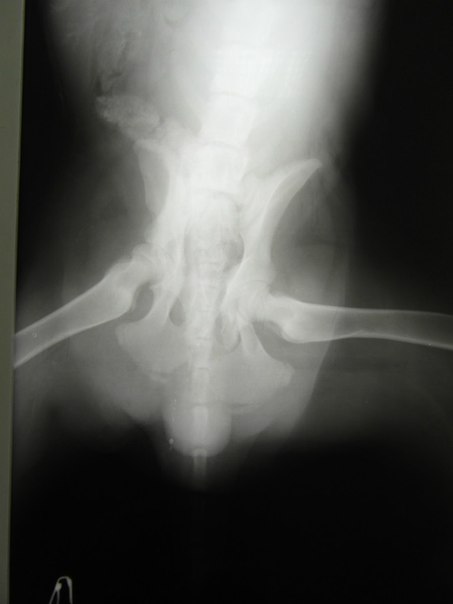

Перелом таза у собаки

Перелом таза у собаки 139 фотографий